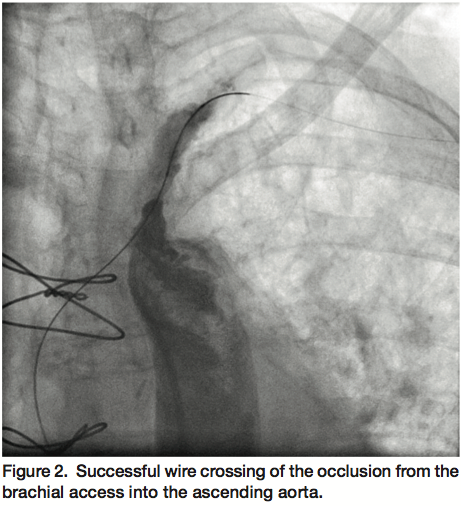

Access was obtained in the left brachial artery and a 25 cm 6 Fr sheath advanced into the subclavian artery for initial angiography, which confirmed a long occlusion of the proximal left subclavian artery (Figure 1) and reversal of flow in the LIMA as well as the left vertebral artery. We attempted to cross the occlusion with a Crosser high-frequency ablation catheter (FlowCardia Inc.), albeit unsuccessfully. Next, a 0.018-inch Astato 30 gm wire (Asahi Intecc) was introduced for a prolonged attempt at recanalization. However, the distal exit point of the subclavian into the aorta was difficult to delineate. For this reason, access was obtained in the right femoral artery and a 6 Fr internal mammary catheter advanced to the ostium of the left subclavian in an attempt at crossing the occlusion from an antegrade approach using another Astato 30 gm wire without success. Ultimately after prolonged manipulation of both Astato wires from retrograde and antegrade approaches, the wire from the brachial access was successful in crossing the occlusion into the ascending aorta (Figure 2). After aggressive balloon angioplasty, a 5 x 19 mm Express stent (Boston Scientific) was deployed in the ostial segment of the subclavian artery followed by a 5 x 15 mm Express stent in an overlapping fashion with care not to jail the LIMA graft, and these stents post-dilated using a 6 x 20 mm Sterling balloon (Boston Scientific). Final angiography performed through the internal mammary catheter revealed significantly improved angiographic result with restoration of antegrade flow through the LIMA (Figure 3).